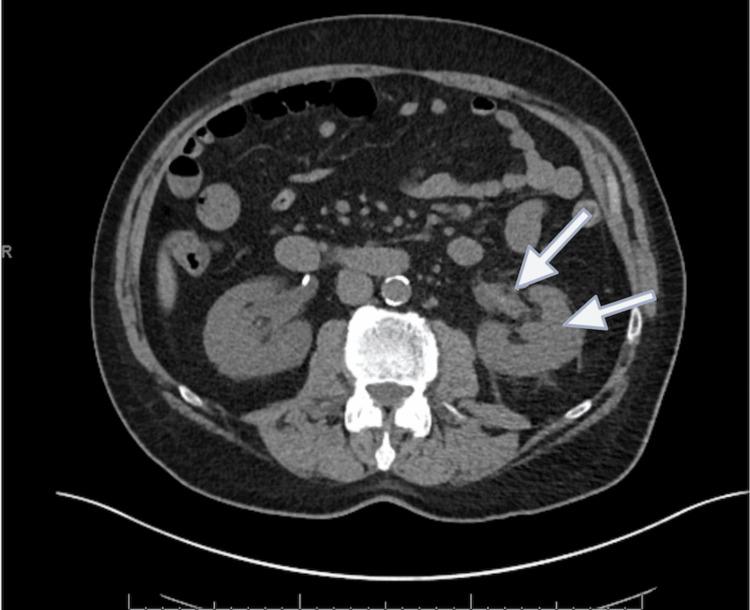

Acquired hemophilia A (AHA) is characterized by the development of neutralizing autoantibodies, called "inhibitors," against intrinsic factor VIII. Its presentation differs profoundly from congenital hemophilia. Here, we present the case of a 69-year-old patient presenting with right-sided flank pain and hematuria, initially diagnosed with acute pyelonephritis, who was found to have bilateral renal hemorrhage during the course of his hospitalization. Later, after a thorough diagnostic evaluation, he was deemed to have AHA.

获得性血友病A(AHA)的特征是产生针对内源性凝血因子VIII的中和性自身抗体,即“抑制剂”。其临床表现与先天性血友病有很大不同。在此,我们报告一例69岁患者,该患者以右侧胁腹疼痛和血尿就诊,最初被诊断为急性肾盂肾炎,在住院期间发现双侧肾出血。后来,经过全面的诊断评估,他被诊断为AHA。